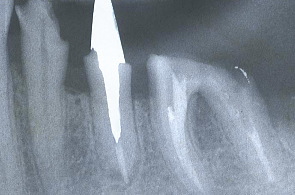

製作した鋳型を口腔内の歯牙に入れ、レントゲンを撮り適合を検査する。

江崎デンタルクリニック、情報公開

下顎の歯牙にも同じようなものを作りレントゲンで根っこを検査した。